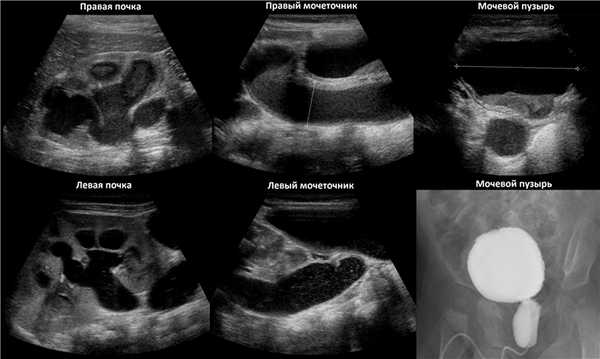

Рисунок. На УЗИ определяется удвоенная чашечно-лоханочная система, расширена лоханка верхнего сегмента (1) и мочеточник на всем протяжение (2, 3), в мочевом пузыре уретроцеле (4). Полное или неполное удвоение чашечно-лоханочной системы возможно увидеть с помощью КТ-урографии.